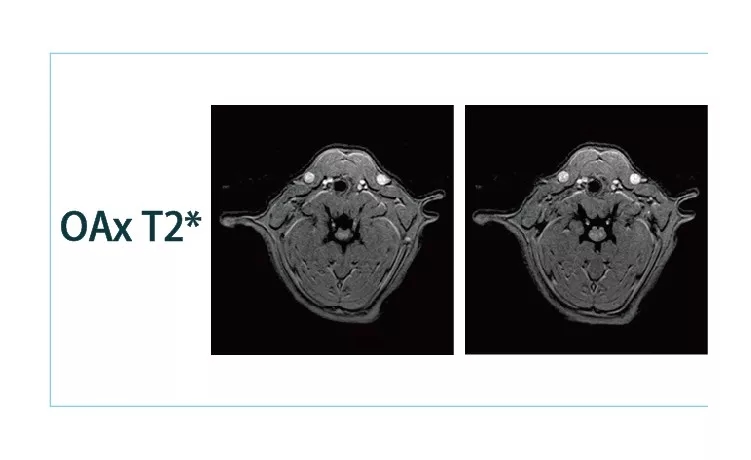

640.webp (3).jpg